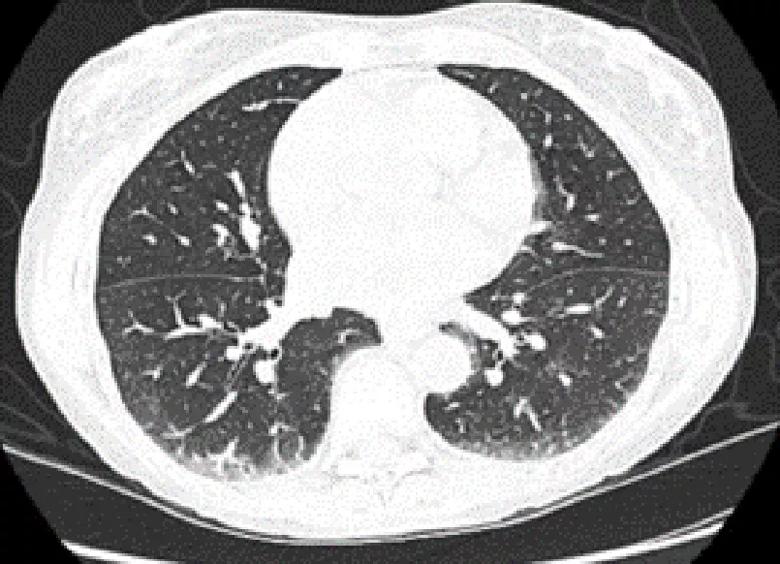

Additional workup included a magnetic resonance imaging (MRI) of her thighs, which showed myositis and computed tomography (CT) of the chest, which showed mild reticulation with ground glass opacity within the lower lobe peripheral lung fields. This was suggestive of interstitial lung disease (ILD) and reduction in diffusion capacity.

A CT chest scan shows changes of nonspecific interstitial pneumonia.

Above, a CT chest scan shows changes of nonspecific interstitial pneumonia.

Below, complete resolution of CT findings can be seen at the patient’s one-year follow-up.